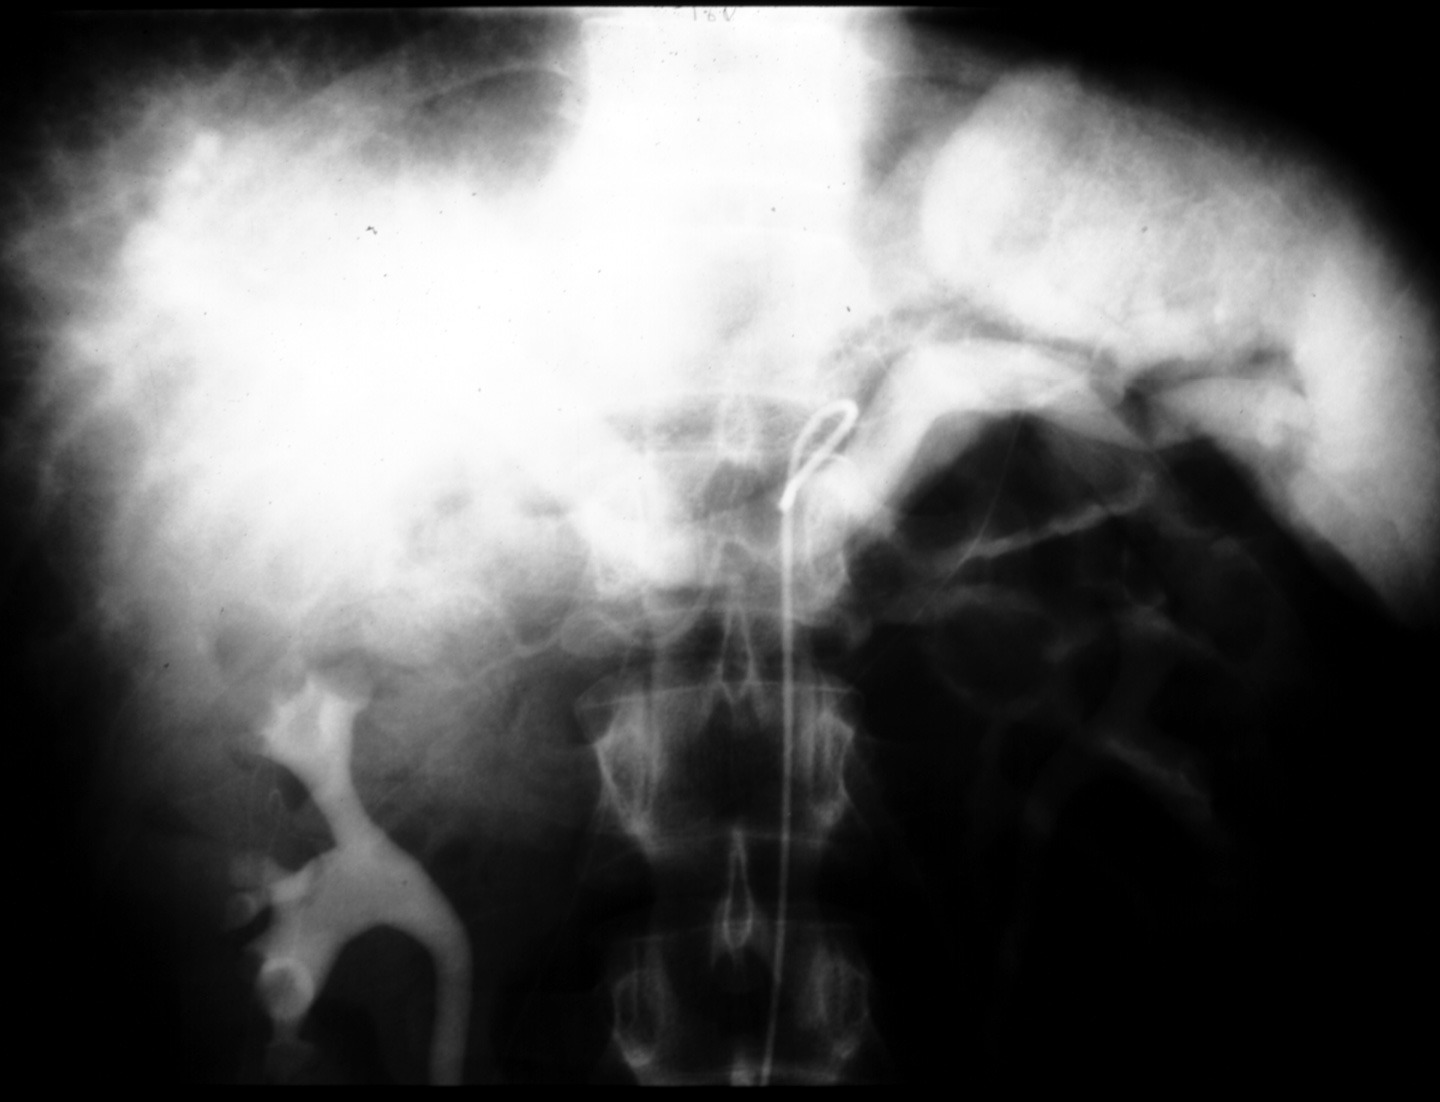

MS I 119 - Celiac Arteriogram (Venous Phase)

Identify:  splenic vein, portal vein, spleen